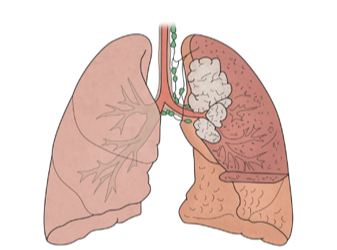

폐암은 국내 암 사망률 1위로, 과거에는 흡연이 폐암의 주요 원인이었지만 최근에는 비흡연자의 폐암 발병이 크게 증가하고 있습니다. 폐암은 오랜 기간 암 사망률 1위를 차지하고 있지만, 의학의 발전으로 생존율이 높아지고 있습니다. 그러나 초기 단계에서 올바르게 관리하는 것이 중요합니다. 폐암의 초기 징후가 무엇인지, 폐암에 좋은 음식은 무엇인지 알아두는 것이 좋습니다.